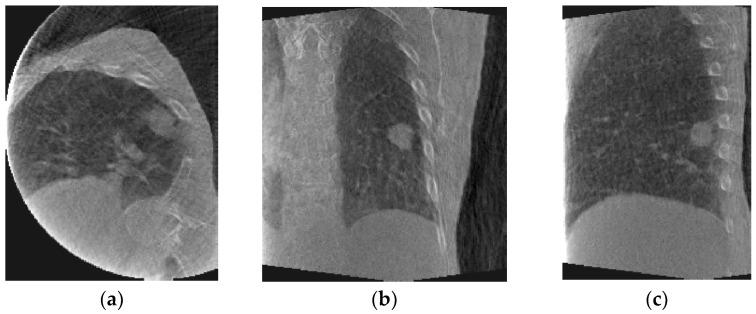

A method for generating fluoroscopic (time-varying) volumetric images using patient-specific motion models derived from four-dimensional cone-beam CT (4D-CBCT) images was developed. 4D-CBCT images acquired immediately prior to treatment have the potential to accurately represent patient anatomy and respiration during treatment. Fluoroscopic 3D image estimation is performed in two steps: (1) deriving motion models and (2) optimization. To derive motion models, every phase in a 4D-CBCT set is registered to a reference phase chosen from the same set using deformable image registration (DIR). Principal components analysis (PCA) is used to reduce the dimensionality of the displacement vector fields (DVFs) resulting from DIR into a few vectors representing organ motion found in the DVFs. The PCA motion models are optimized iteratively by comparing a cone-beam CT (CBCT) projection to a simulated projection computed from both the motion model and a reference 4D-CBCT phase, resulting in a sequence of fluoroscopic 3D images. Patient datasets were used to evaluate the method by estimating the tumor location in the generated images compared to manually defined ground truth positions. Experimental results showed that the average tumor mean absolute error (MAE) along the superior-inferior (SI) direction and the 95th percentile in two patient datasets were 2.29 and 5.79 mm for patient 1, and 1.89 and 4.82 mm for patient 2. This study demonstrated the feasibility of deriving 4D-CBCT-based PCA motion models that have the potential to account for the 3D non-rigid patient motion and localize tumors and other patient anatomical structures on the day of treatment.

开发了一种使用从四维锥形束CT(4D-CBCT)图像导出的患者特定运动模型来生成荧光透视(随时间变化)体积图像的方法。在治疗前立即采集的4D-CBCT图像有可能准确地反映治疗期间患者的解剖结构和呼吸情况。荧光透视三维图像估计分两步进行:(1)推导运动模型和(2)优化。为了推导运动模型,使用可变形图像配准(DIR)将4D-CBCT集中的每个相位配准到从同一集中选择的参考相位。主成分分析(PCA)用于将DIR产生的位移向量场(DVF)的维度降低为几个表示DVF中发现的器官运动的向量。通过将锥形束CT(CBCT)投影与从运动模型和参考4D-CBCT相位计算出的模拟投影进行比较,对PCA运动模型进行迭代优化,从而生成一系列荧光透视三维图像。使用患者数据集通过将生成图像中的肿瘤位置与手动定义的真实位置进行比较来评估该方法。实验结果表明,在两个患者数据集中,患者1沿上下(SI)方向的平均肿瘤平均绝对误差(MAE)和第95百分位数分别为2.29和5.79毫米,患者2为1.89和4.82毫米。这项研究证明了推导基于4D-CBCT的PCA运动模型的可行性,该模型有可能考虑三维非刚性患者运动,并在治疗当天对肿瘤和其他患者解剖结构进行定位。